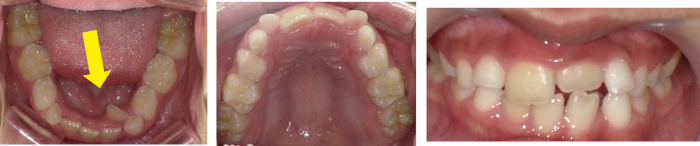

症例(1)

利府町の矯正相談の患者さん 8歳6か月 女性

① 左下前歯が内側から生えてきて、本人・母親・父親が気になる。

(一番聞きたい事)

料金・期間・矯正しない場合の影響について聞きたいです。

診断名:下顎側切歯舌側転位を伴う上下顎前歯部叢生

?で判断します。この患者さんの場合は、下顎前歯が内側に生えているために、舌が動かし辛くなっています。そのため、食べる時の飲み込み、発音、睡眠等に影響を与える状態です。

下顎前歯内側に生えている状態を改善しなければ、身体の発育に影響する可能性があります。顎の成長期間は限られており、中学卒業までに90%の成長が終了するため、早期に介入することにより顎の成長を促す期間が長く確保できます。

この患者さんの場合は、歯の生える場所がありませんので、この期間を長く確保する必要があります。